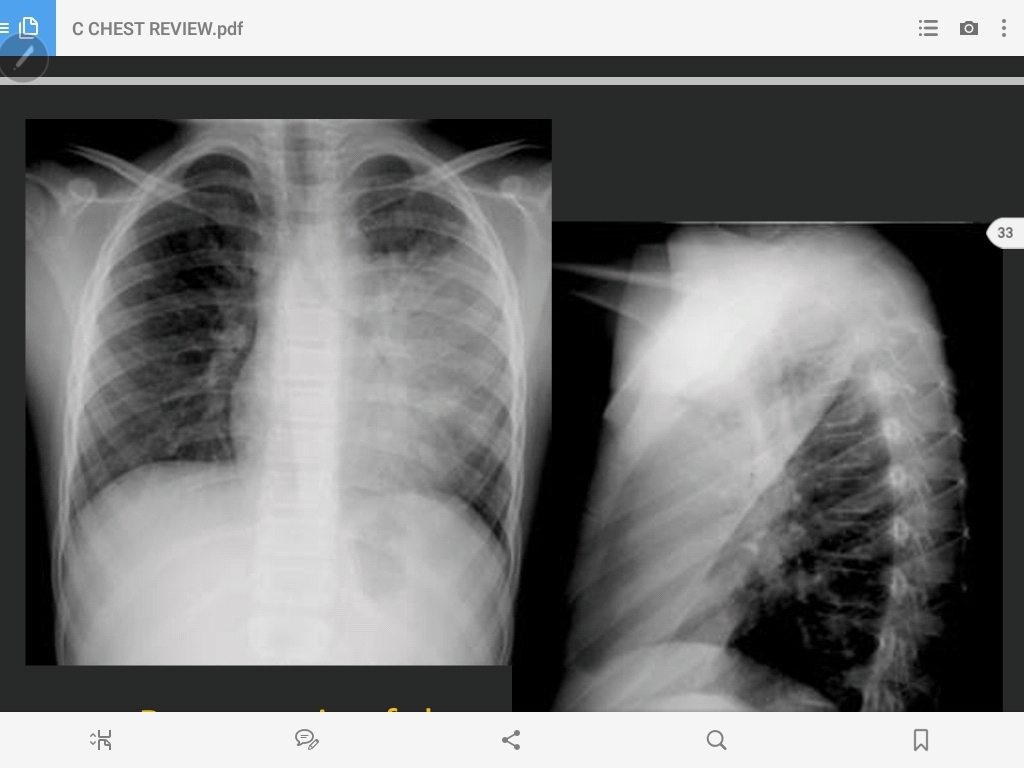

pneumonia of the left upper lobe

lingular pneumonia